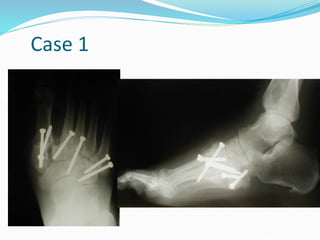

Case 1